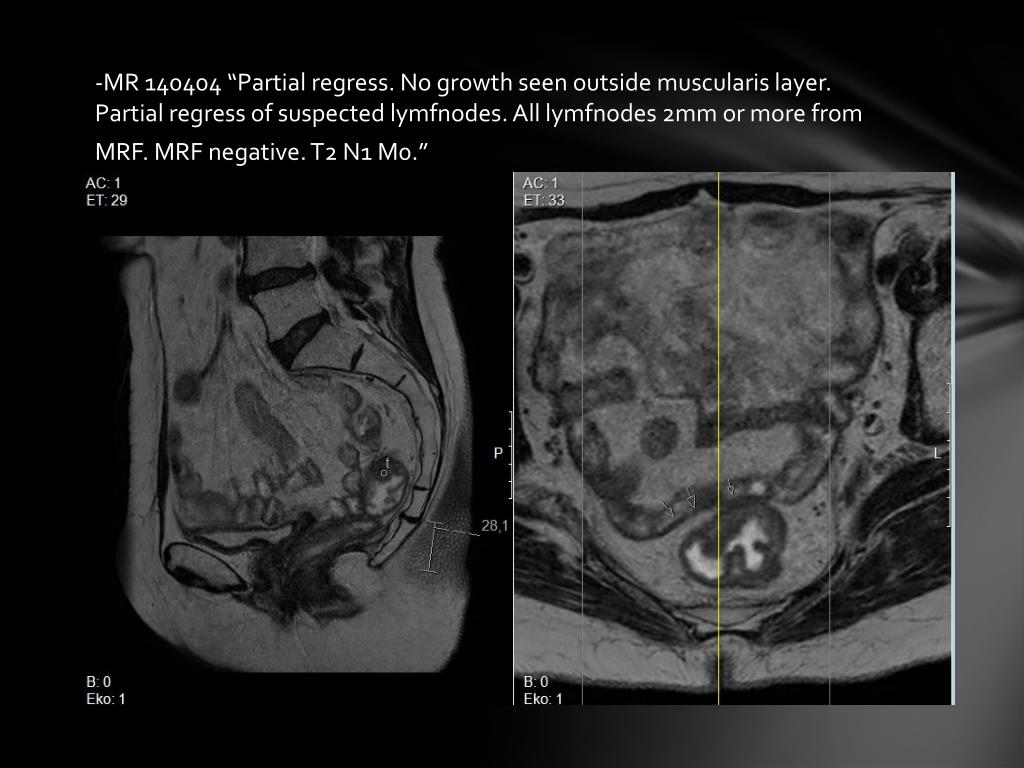

7. -MR 140404 “Partial regress. No growth seen outside muscularis layer. Partial regress of suspected lymfnodes. All lymfnodes 2mm or more from MRF. MRF negative. T2 N1 M0.”